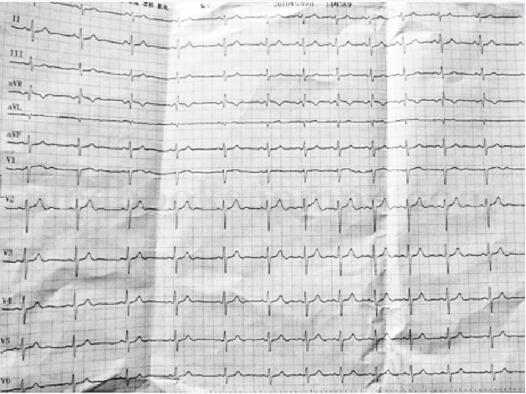

患者经过电复律治疗3天后,查体:血压110/70mmHg,双肺呼吸音清,无干湿性啰音,心率62次/分,律齐,未闻及病理性杂音。腹软,双下肢无水肿。既往发现右室心肌病2年,已行ICD治疗,近几月反复发作室速,原因有以下可能:①胺碘酮用量即维持量不足;②感染,胺碘酮静滴可能引起静脉炎。入院后给予患者倍他洛克加量,血压控制尚可,心电图检查结果(图61-2)。

图61-2 调整治疗方案治疗3天后的心电图所见